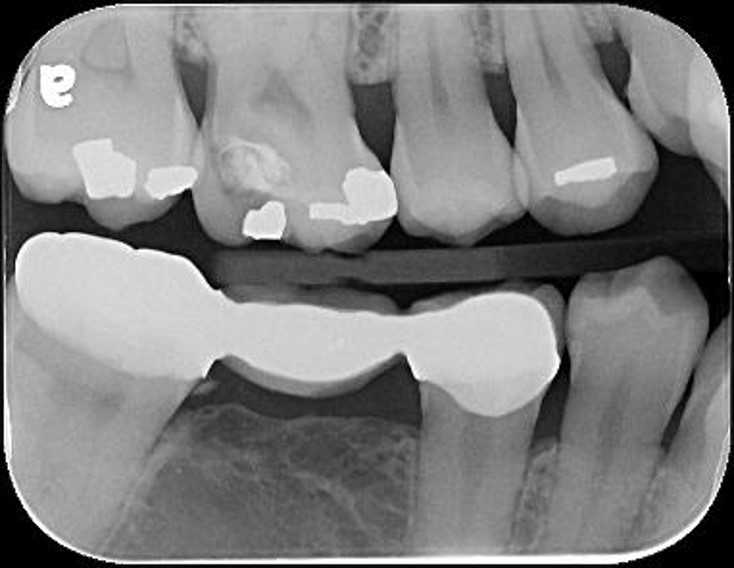

通常患者的蛀牙都在鄰接面、牙齦下,因此傳統必須進行根管治療等治療,但如果沒有蛀至牙髓,早期將牙齦下蛀牙以水雷射切除蛀牙與牙髓,戴上臨時假牙觀察一個月,如果沒有牙髓相關症狀,接著再印模製作假牙,而現今全鋯冠硬度與美觀都相當理想,為現今治療的最前線治療。

治療前,右上第一大臼齒疼痛

治療前,第一大臼齒蛀牙